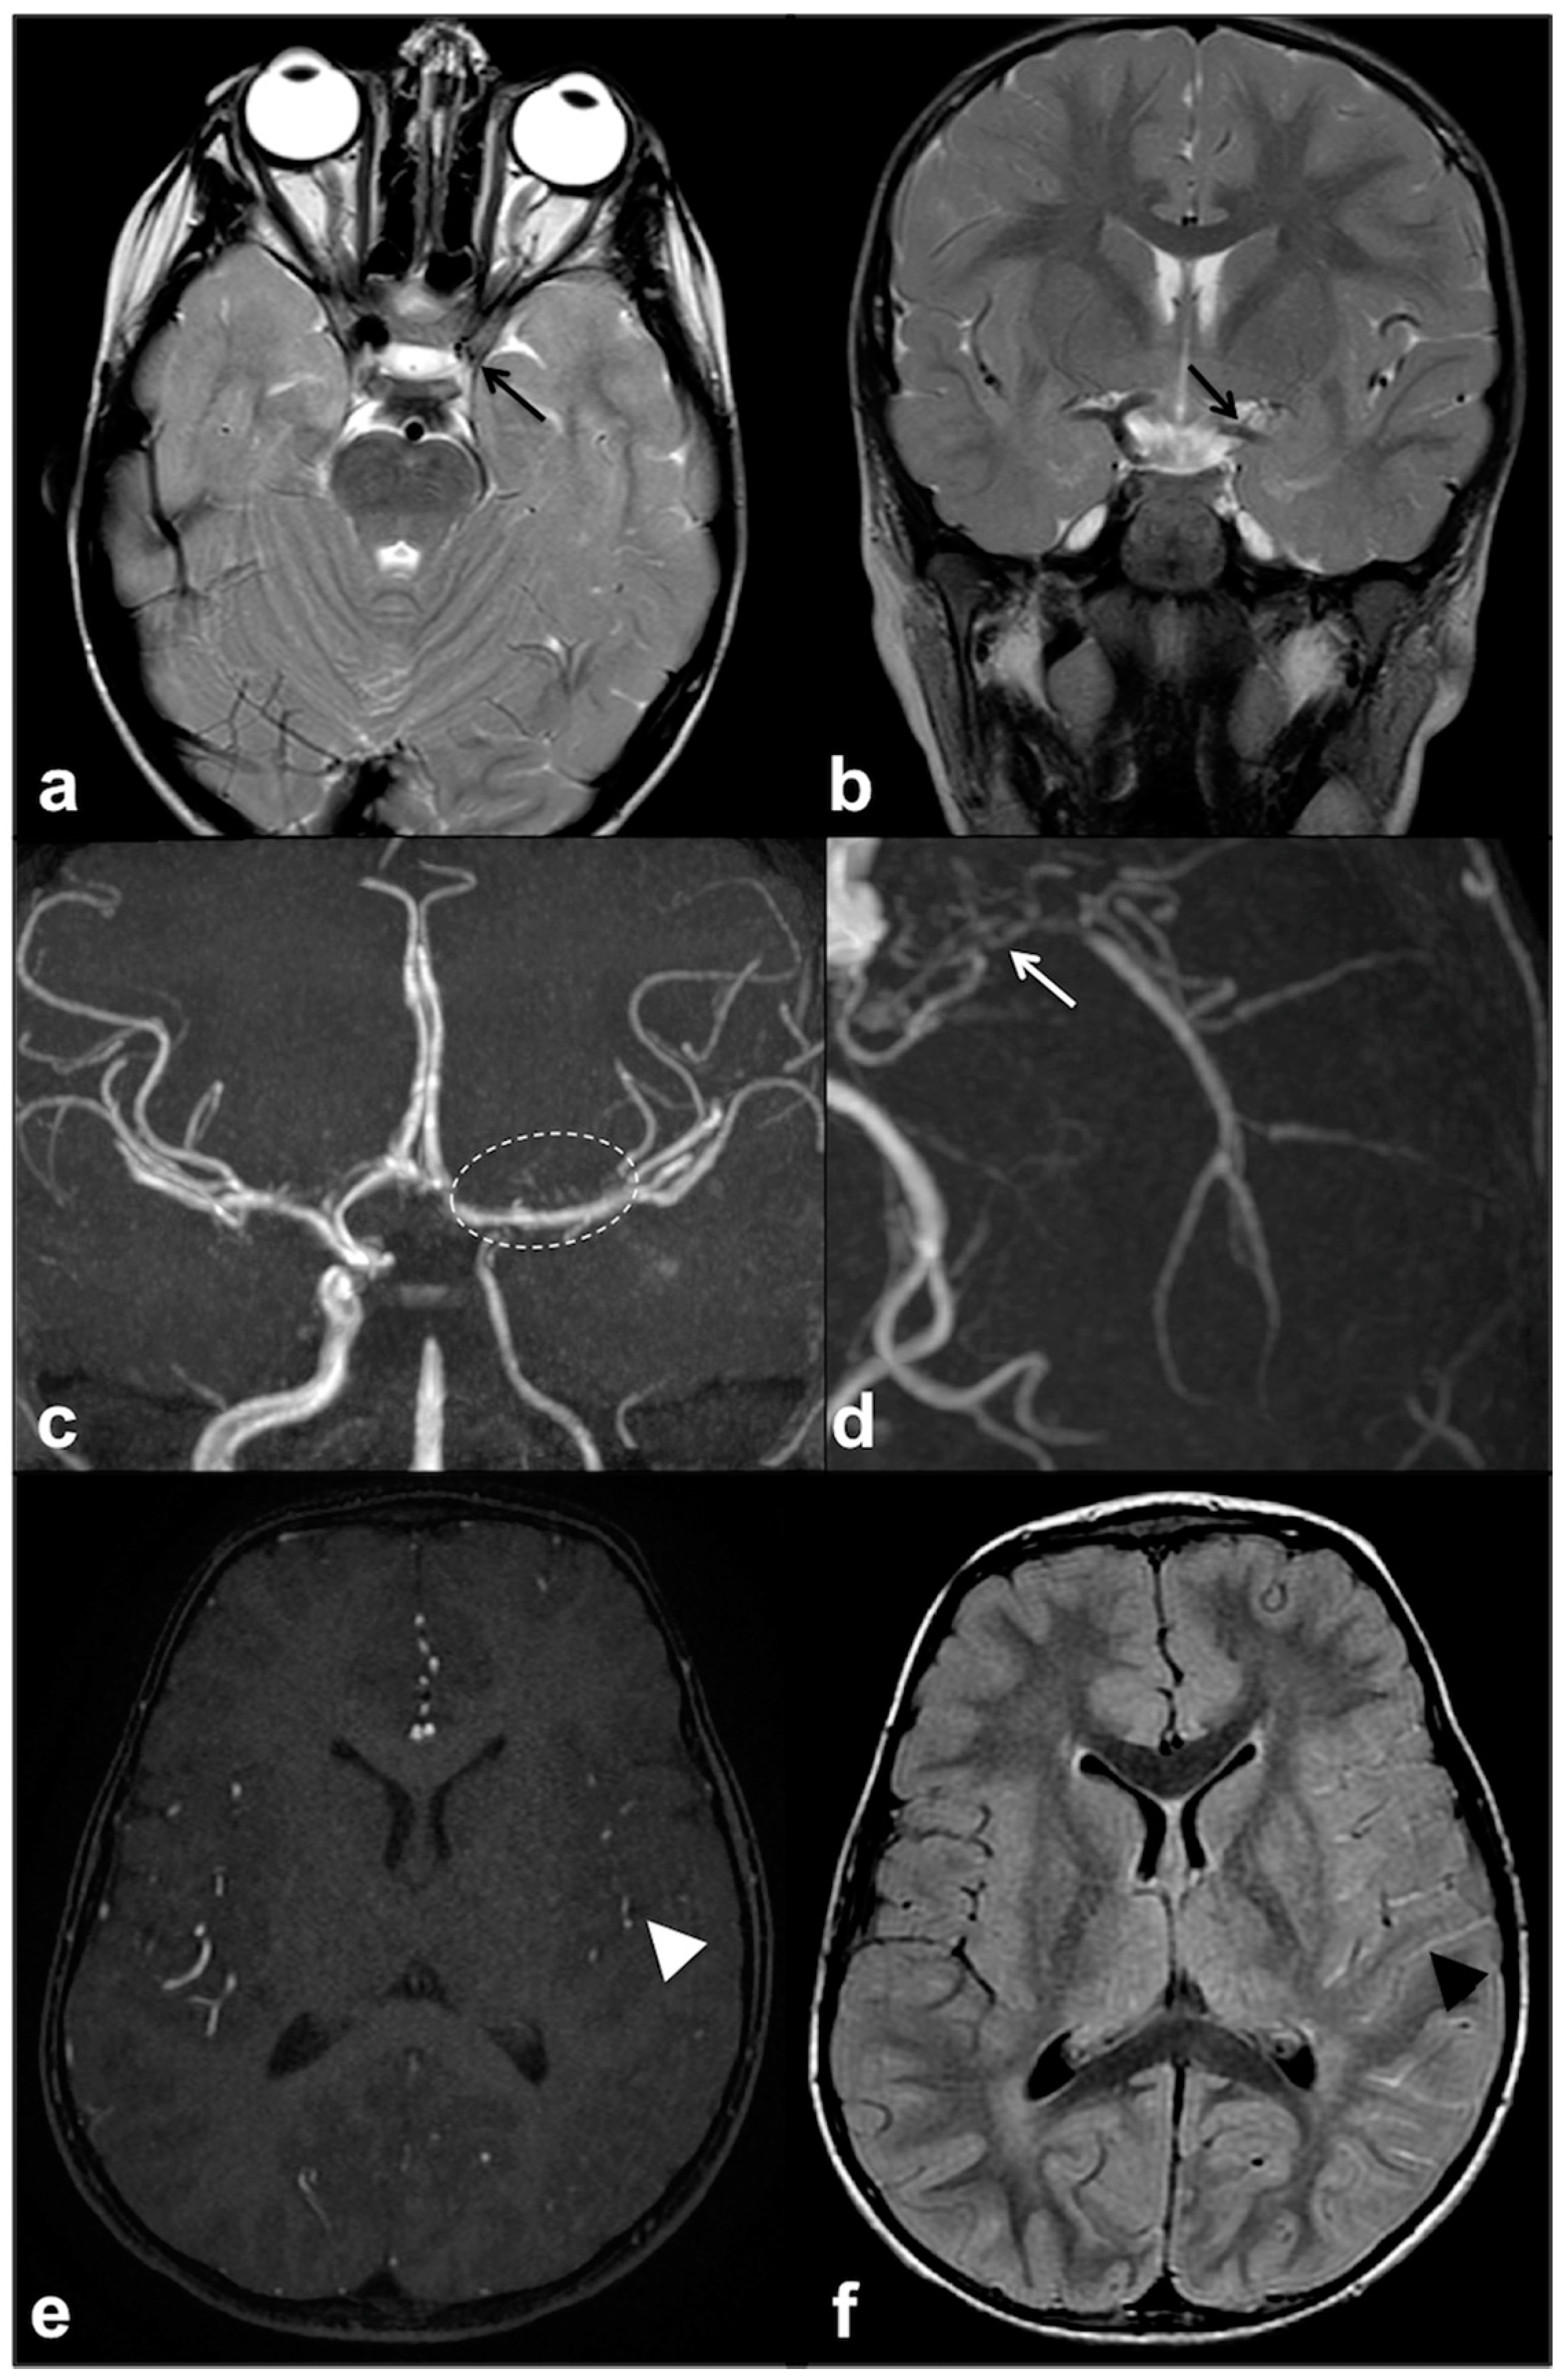

2.3. Epileptogenic Lesions in NF1

- Bernardo, P.; Santoro, C.; Rubino, A.; Mirone, G.; Cinalli, G. Epilepsy surgery in neurofibromatosis type 1: An overlooked therapeutic approach. Child’s Nerv. Syst. 2020, 36, 2909–2910. [Google Scholar] [CrossRef] [PubMed]

- Pecoraro, A.; Arehart, E.; Gallentine, W.; Radtke, R.; Smith, E.; Pizoli, C.; Kansagra, S.; Abdelnour, E.; McLendon, R.; Mikati, M.A. Epilepsy & Behavior Epilepsy in neurofibromatosis type 1. Epilepsy Behav. 2017, 73, 137–141. [Google Scholar]

- Ostendorf, A.P.; Gutmann, D.H.; Weisenberg, J.L.Z. Epilepsy in individuals with neurofibromatosis type 1. Epilepsia 2013, 54, 1810–1814. [Google Scholar] [CrossRef] [PubMed]

- Bernardo, P.; Cinalli, G.; Santoro, C. Epilepsy in NF1: A systematic review of the literature. Child’s Nerv. Syst. 2020, 36, 2333–2350. [Google Scholar] [CrossRef] [PubMed]

- Hsieh, H.-Y.; Fung, H.-C.; Wang, C.-J.; Chin, S.-C.; Wu, T. Epileptic seizures in neurofibromatosis type 1 are related to intracranial tumors but not to neurofibromatosis bright objects. Seizure 2011, 20, 606–611. [Google Scholar] [CrossRef] [PubMed]

- Barba, C.; Jacques, T.; Kahane, P.; Polster, T.; Isnard, J.; Leijten, F.S.; Özkara, Ç.; Tassi, L.; Giordano, F.; Castagna, M.; et al. Epilepsy surgery in Neurofibromatosis Type 1. Epilepsy Res. 2013, 105, 384–395. [Google Scholar] [CrossRef] [PubMed]